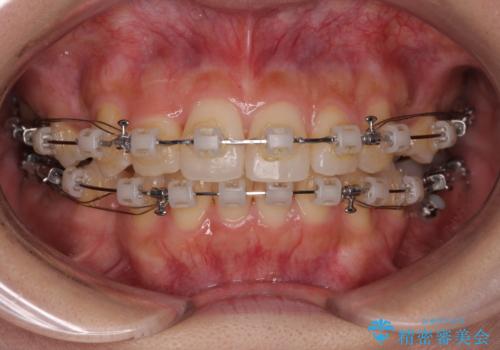

- 矯正装置

- クリアブラケット

上下左右の第一小臼歯4本を抜歯して治療を行うことがセオリーでしたが、左下は第二小臼歯が銀歯であったため、イレギュラーではありますが、そちらを抜歯しました。

その影響で治療期間は長くなりましたが、処置していない歯を保存することができました。